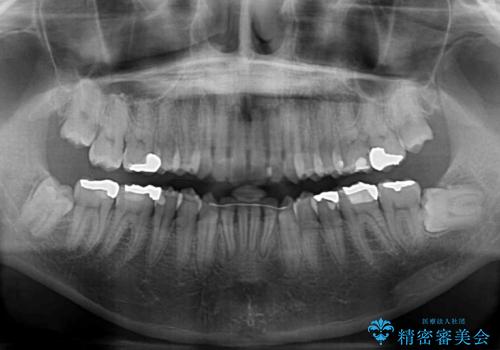

- 前歯のデコボコを気にして来院された患者様です。

下顎前歯のデコボコが特に強く、治療を早く終えることを考えるとワイヤー装置がお勧めですが、ワイヤー装置の異物感は避けたいのでインビザラインを希望されていました。

インビザラインで治療を行うか、ワイヤーで治療を行うかずっと悩んでいらっしゃいましたが、早く終わらせることを優先してワイヤー装置にて治療を行うこととしました。

下顎にワイヤー装置を装着し、暫くしたところでやはりインビザラインにて矯正治療をしたいとのことで、インビザラインに切り替えました。

短い期間でしたがワイヤー装置を使用したことでデコボコが解消されたため、インビザラインの比較的短い期間で矯正治療を行うことができました。